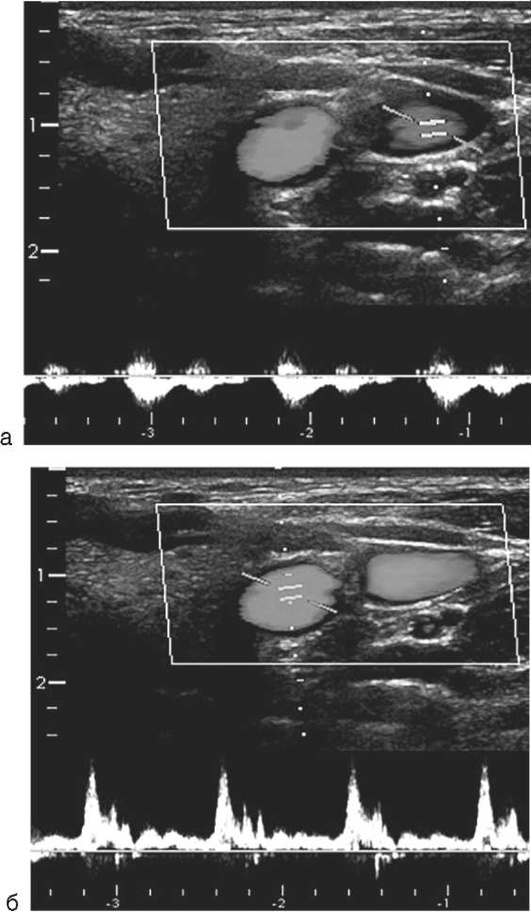

• Ультразвук, по современным клиническим рекомендациям, рассматривается как альтернатива при отсутствии капнометрии. Верифицируют ультразвуковые признаки скольжения легких (скольжение в В-режиме; признак «морской берег» в М-режиме), появление Z-линий (вертикальных гиперэхо-генных коротких быстрозатухающих артефактов) и В-линий (вертикальных длинных гиперэхогенных артефактов). Верификация этих признаков свидетельствует о вентиляции легких: с обеих сторон - при правильном положении интубационной трубки, с одной стороны - при смещении трубки в бронх (рис. 2.46). При неправильной интубации визуализируют эндотрахеальную трубку, расположенную в пищеводе.

pic 0055

Рис. 2.46. Ультразвуковые признаки эффективной вентиляции легких: признаки скольжения легких в В-режиме (а), М-режиме (в); Z-линии (а), В-линии (б)